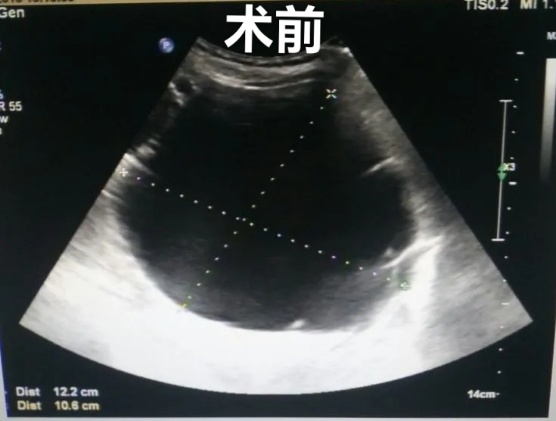

2、超声引导下囊肿抽液硬化治疗,肝囊肿、肾囊肿穿刺抽液硬化治疗,盆腔囊肿穿刺抽液硬化治疗,甲状腺、乳腺囊肿穿刺抽液治疗。

肝囊肿经皮超声引导性介入治疗